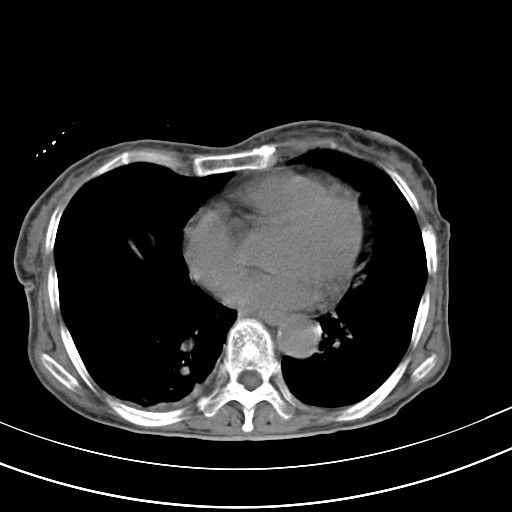

病人上腹部胀痛拌全身黄染八天

右侧少量胸水,胆囊增大,肝内胆管扩张,肝门部结构杂乱,建议增强。

右侧胸腔少量积液,右下叶结节灶,。

肝内胆管及胰管扩张考虑为胰头区占位,肝门淋巴结增多,肝内多发低密度影,考虑为转移。门脉高压,脾大,胆囊大。

肝内胆管及胰管扩张,胰头增大考虑为胰头区占位,肝门淋巴结增多,考虑为转移。建议增强,脾大,胆囊大,壁厚,慢性胆囊炎。胃壁好像也增厚,且有一肿物。

1)考虑胰头癌并胆系低位梗阻;建议行ct增强扫描检查。2)慢性胆囊炎。3)脾大。4)少量腹水。5)双侧少量胸腔积液。